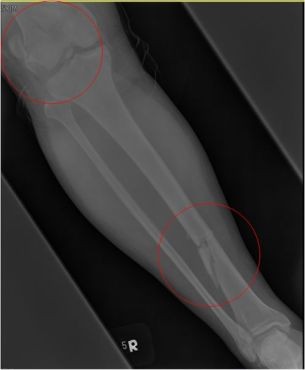

圖:鄺世通醫師分享當時洪國程先生右腳多處粉碎性骨折。

而當時的主治醫師就是個性直率低調,被同事與後進同仁暱稱為鄺爺的骨科鄺世通醫師,這個在鄺醫師口中的小骨折,其實是包含髖關節、大腿股骨、膝蓋髕骨、與小腿脛骨等多處粉碎性骨折的複雜個案,不論是X光檢查,還是電腦斷層檢查,都能看見因為強力撞擊穿出髖關節的股骨,還有粉碎的髕骨,歷經數個小時的開刀,才救回洪國程先生的性命與右腿。